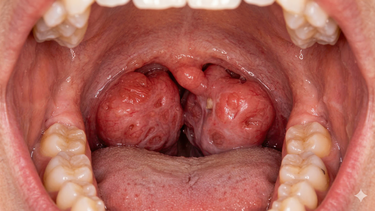

Hình ảnh qua nội soi tai mũi họng

Khi nội soi, bác sĩ có thể nhận thấy một số đặc điểm sau:

- Niêm mạc vòm họng xuất hiện vùng dày lên nhẹ, màu sắc thay đổi so với xung quanh.

- Có thể thấy mảng sùi nhỏ, phẳng hoặc hơi gồ, bề mặt không đều.

- Một số trường hợp xuất hiện vết trợt, loét nông, dễ chảy máu khi chạm vào.

Những hình ảnh này khác với viêm họng thông thường ở chỗ tổn thương thường khu trú một bên, không đối xứng và không cải thiện sau điều trị kháng viêm thông thường.